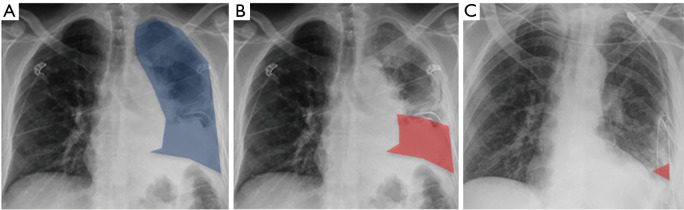

For each patient, we recorded the morbidity, mortality, PPE treatment failure and additional procedures required, germ identification and type, inflammatory syndrome, C-reactive protein level, CRP, and Leucocyte counts before treatment initiation (surgery or fibrinolysis) and at the end of the treatment (day of discharge, if before day 7, or day 7). Patient co-morbidities were also recorded. For each patient, we also assessed the percentage of lung area occupied by pleural opacity on chest X-ray before treatment initiation and at the end of the treatment (day of discharge, if before day 7 or day 7). All chest X-rays used for this part of the study were performed on patients either standing up or sitting in the upright position (no X-rays in bed with lying patients). For this, we choose an approach that was similar to the MIST2 trial (7). Two blinded medical doctors assessed the pleural opacity over time and the results were pooled (Figure 1). This allowed an objective quantification of pleural opacity change over time. In the surgical group, we deliberately chose to compare discharge X-ray and not immediate postoperative X-ray to avoid bias caused by important lung recruitment with positive airway pressure.

Figure 1.

X-ray analysis performed in the surgery and fibrinolysis groups. (A) Total hemithorax (highlighted in blue) area that contains the loculated pleural effusion. Landmarks used were the spine, the lateral edge of the chest wall, the diaphragm and the heart silhouette. (B) Pleural effusion (highlighted in red) area at day 0 before therapy. (C) Pleural effusion (highlighted in red) at day 7 following therapy (either surgical or fibrinolytic).